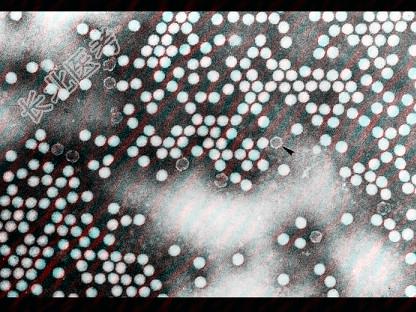

- 多项选择题关于图中所示的脊髓灰质炎病毒,正确的是 ( )

A、能抵抗乙醚、乙醇和胆盐,在pH值3.0~10环境中活力稳定

B、脊髓灰质炎病毒是单股RNA,直径16 nm

C、对热、干燥及氧化消毒剂敏感

D、在大便、污水中仅可存活1~2个月

E、有3型病毒,世界各地流行以Ⅰ型居多